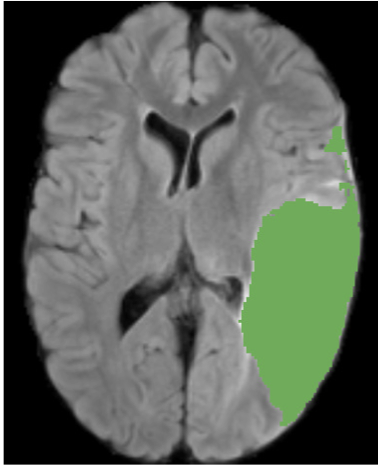

Parallel Capsule Net for Ischemic Stroke Segmentation

MD Sharique, Uday Bondi Pundarikaksha, Pradeeba Sridar, R S Ramakrishnan, R Krishnakumar

Pre-print on bioRxiv

A novel neural network architecture, Parallel Capsule Net (PCN) for segmentation of Ischemic Stroke.